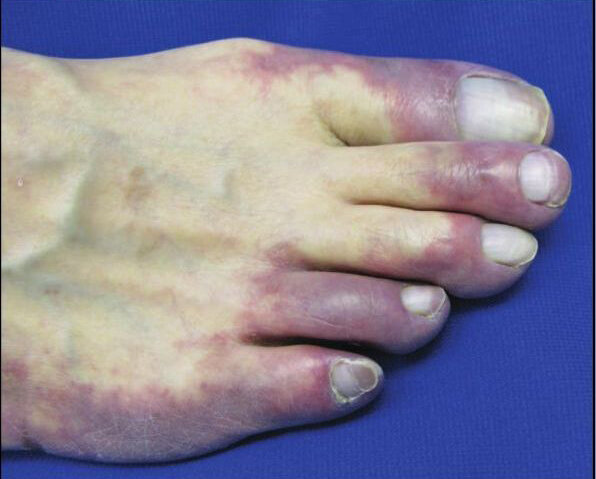

Iskemia tungkai akut atau Acute Limb ischemia (ALI) adalah terjadinya penurunan aliran darah di tungkai dikarenakan adanya sumbatan. Penyebab utama ALI adalah karena thromboemboli, atau bekuan darah yang timbul akibat gangguan irama pada jantung dan dibawa oleh aliran darah ke tungkai. Hal ini dapat berakibat pada matinya jaringan di kaki dan dapat berakhir dengan amputasi.

Klinis: Gejala klinis ALI ditandai dengan 6P yaitu:

• pain (rasa nyeri)

• paraesthesia (sensasi berkurang)

• paralysis (kelemahan pada tungkai)

• pallor (pucat)

• pulselessness (nadi tidak teraba)

• poikilotermia (rasa dingin di kaki)

Diagnosis dan penanganan ALI harus dilakukan dengan cepat, karena bila dilakukan lebih dari 6 jam maka akan terjadi kerusakan jaringan yang ireversibel dan bisa berakhir dengan amputasi. Setelah melakukan diagnosis, maka dokter bedah vaskular dapat memberikan obat-obatan untuk menghancurkan bekuan darah yang menyumbat, melakukan tindakan operasi minimal invasive melalui endovaskular untuk mengeluarkan bekuan darah, ataupun melalui pembedahan.